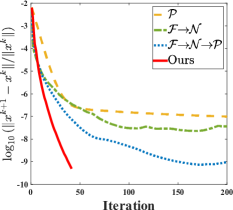

As shows in Fig. 1, at the first several iterations, the loss of is slightly larger than that of . Because the input is corrupted with severe artifacts, thus the role of data-driven module is significant at the first several steps. But as process goes on, repeated denoising operation in turn causes over-smoothing. While module can make up for it by incorporating model based knowledge. Though can improve the performance, it cannot ideally converge to a desired solution. The solid line indicates the superiority of Ours over other choices in both convergence rate and reconstruction accuracy. The execution time of , , and Ours is 4.4762s, 3.3240s, 6.2760s and 2.5225s, respectively. As expect, the proposed method provides a much faster reconstruction process. Thus we can verify that our framework has higher efficiency both in terms of theoretical convergence and practical execution time. The visualized results in Fig. 2 also verify that Ours has better performance than others.